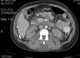

Renal cortical necrosis (RCN) is a rare cause of acute kidney failure. The condition is "usually caused by significantly diminished arterial perfusion of the kidneys due to spasms of the feeding arteries, microvascular injury, or disseminated intravascular coagulation" and is the pathological progression of acute tubular necrosis. [Source: Wikipedia ]